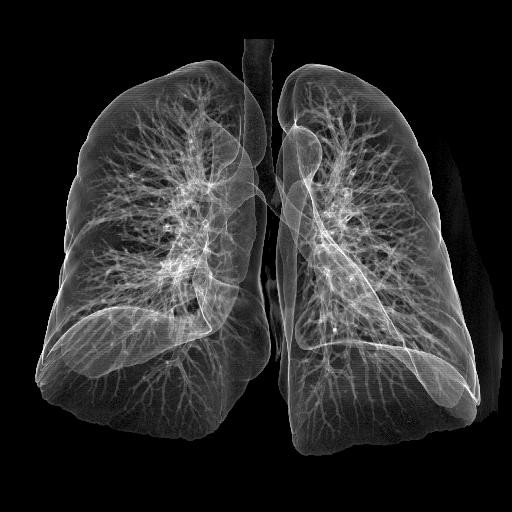

Medical Dry Thermal PET X Ray Film , Agfa Drystar DT2B Fuji Drypix

Picture

Medical Dry Thermal PET X Ray Film , Agfa Drystar DT2B Fuji Drypix Images |